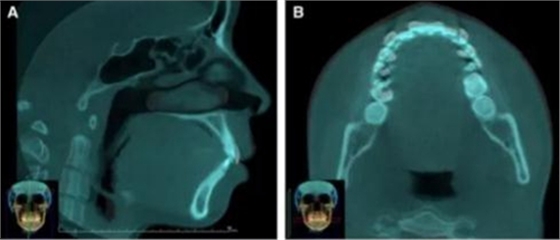

2.由于患者有較高的美學(xué)要求,且無法忍受拔牙后缺牙情況,在上頜尖牙遠(yuǎn)中使用橋體修復(fù),使用雙J鉤提供上頜前牙矯治力,早期舌側(cè)矯治時(shí)使用墊片替代網(wǎng)架,為使力通過阻抗中心,前牙臂鉤距墊片約20mm。后臂鉤從尖牙冠舌側(cè)延長,該裝置結(jié)合橡皮鏈圈或超彈絲用以關(guān)閉間隙,后側(cè)鉤也可以結(jié)合II類牽進(jìn)行轉(zhuǎn)矩控制。該病例中為了減小上頜后牙伸長,患者必要時(shí)僅在夜間佩戴II類牽。使用Transbond粘接劑粘接舌側(cè)裝置。于腭部植入3枚TAD(2枚直徑1.6mm長8mm;腭中縫處1枚直徑1.6mm長7mm),使用鏈圈連接(每側(cè)提供200g力關(guān)閉間隙,每側(cè)60g力壓低)。(圖3)從生物力學(xué)角度,鉤子的位置能改變力與阻抗中心的關(guān)系從而決定牙齒是內(nèi)收還是壓低。舌側(cè)內(nèi)收時(shí),上頜左后種植釘脫落,因此在左上頜第二前磨牙與第一磨牙間植入TAD(直徑1.6mm長8mm)。6月后,前牙內(nèi)收效果顯著,尖牙及第二前磨牙間僅存在1-1.5mm空間。此時(shí)患者滿意治療效果,同意使用固定矯治器進(jìn)行軸向控制及控根。雙頜牙弓使用0.022×0.028-in陶瓷托槽,排齊后使用0.018×0.025-in不銹鋼絲維持上頜牙弓關(guān)閉間隙,此時(shí)患者要求上唇更加內(nèi)收,因此將上頜切牙適當(dāng)舌傾。(圖3)

該患者在6顆上前牙區(qū)使用雙J鉤片段弓,水平臂均用0.028-in不銹鋼絲制成,作用力在臂的最末端,力的模擬見圖4。使用該方法能夠模擬正畸時(shí)受到的力。文獻(xiàn)表明,TAD深度8mm為佳,前牙阻抗中心由牙齒移動模式?jīng)Q定水平臂的末端而決定。圖4顯示了6顆前牙在內(nèi)收4mm后牙周膜的應(yīng)力分布。當(dāng)力的延長線通過6顆牙的阻抗中心是,牙齒整體移動且壓低0.5mm,當(dāng)其處于阻抗中心冠方時(shí),前牙舌傾,當(dāng)其處于根方時(shí),根舌向移動。(圖5)